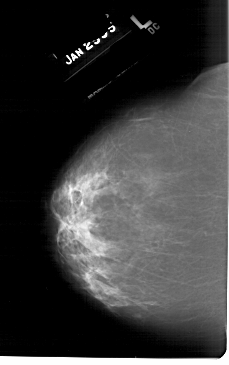

ics_version 1.0 filename A-1265-1 DATE_OF_STUDY 25 1 1995 PATIENT_AGE 48 FILM FILM_TYPE REGULAR DENSITY 3 DATE_DIGITIZED 23 7 1998 DIGITIZER HOWTEK 43.5 SEQUENCE LEFT_CC LINES 6556 PIXELS_PER_LINE 4111 BITS_PER_PIXEL 12 RESOLUTION 43.5 NON_OVERLAY LEFT_MLO LINES 6616 PIXELS_PER_LINE 4081 BITS_PER_PIXEL 12 RESOLUTION 43.5 NON_OVERLAY RIGHT_CC LINES 6646 PIXELS_PER_LINE 4066 BITS_PER_PIXEL 12 RESOLUTION 43.5 OVERLAY RIGHT_MLO LINES 6871 PIXELS_PER_LINE 3961 BITS_PER_PIXEL 12 RESOLUTION 43.5 OVERLAY |

FILE: A_1265_1.RIGHT_CC.OVERLAY TOTAL_ABNORMALITIES 1 ABNORMALITY 1 LESION_TYPE CALCIFICATION TYPE PLEOMORPHIC DISTRIBUTION CLUSTERED LESION_TYPE MASS SHAPE IRREGULAR MARGINS ILL_DEFINED ASSESSMENT 4 SUBTLETY 3 PATHOLOGY BENIGN TOTAL_OUTLINES 1 BOUNDARY |